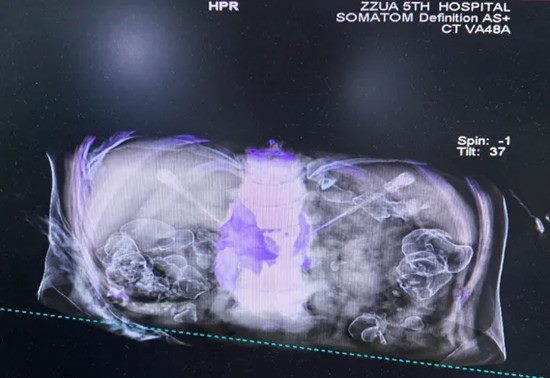

640 (2)_副本

▲ 注射靶点影像